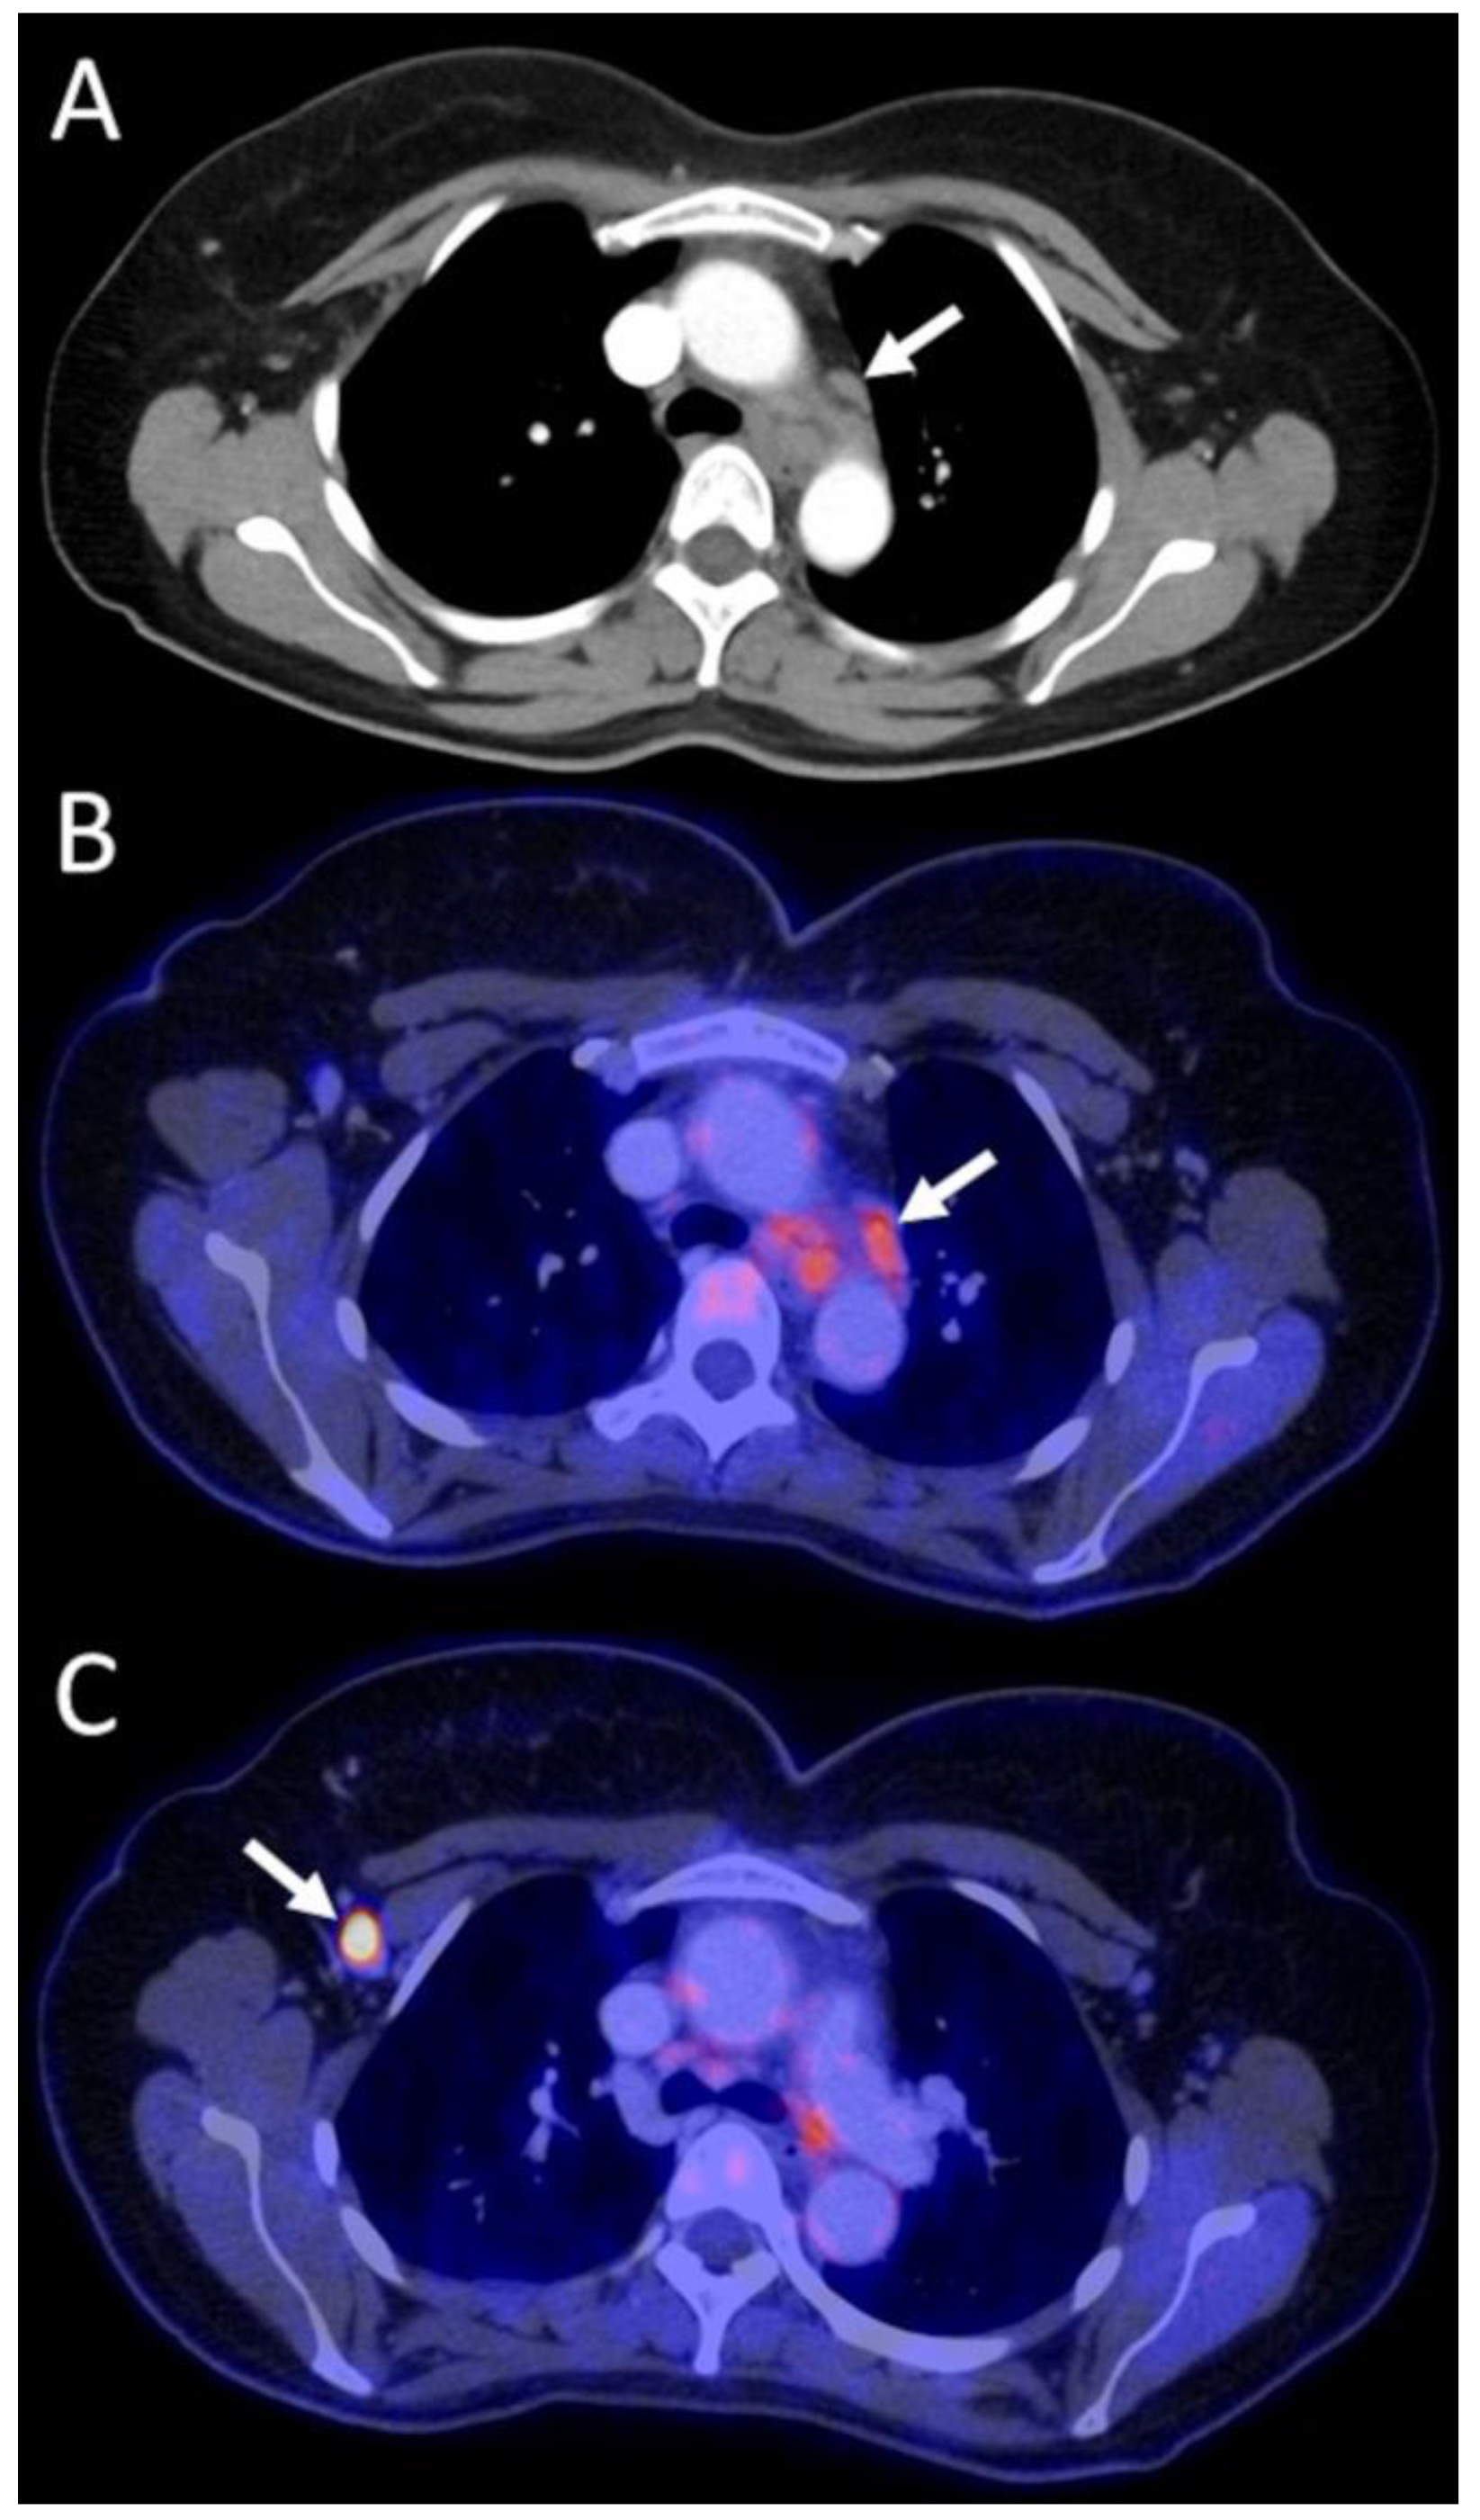

3.4.1. Primary Staging Patients (n = 15/52)

| Group A Staging (n = 15 scans in 15 patients) | Stage I: n = 3 Stage II: n = 6 Stage III: n = 5 Stage IV: n = 1 | surgery + systemic | surgery + systemic | P | C | downstaging, IV → I | yes, invasive | 1 | Major (n = 6) | better customized therapy, major psychological benefit of downstaging, avoidance of invasive tests |

| downstaging, IV → IIa | 1 | |||||||||

| surgery + systemic + RTX | surgery + systemic + RTX | P | C | downstaging, IV → IIb | no | 2 | better customized therapy, major psychological benefit of downstaging | |||

| systemic | systemic | P | C | downstaging, IV → IIIa | yes, invasive | 1 | better customized therapy, major psychological benefit of downstaging, avoidance of invasive tests | |||

| systemic + RTX | systemic + RTX | P | C | downstaging, IV → I | yes, invasive | 1 | better customized therapy, major psychological benefit of downstaging, avoidance of invasive tests | |||